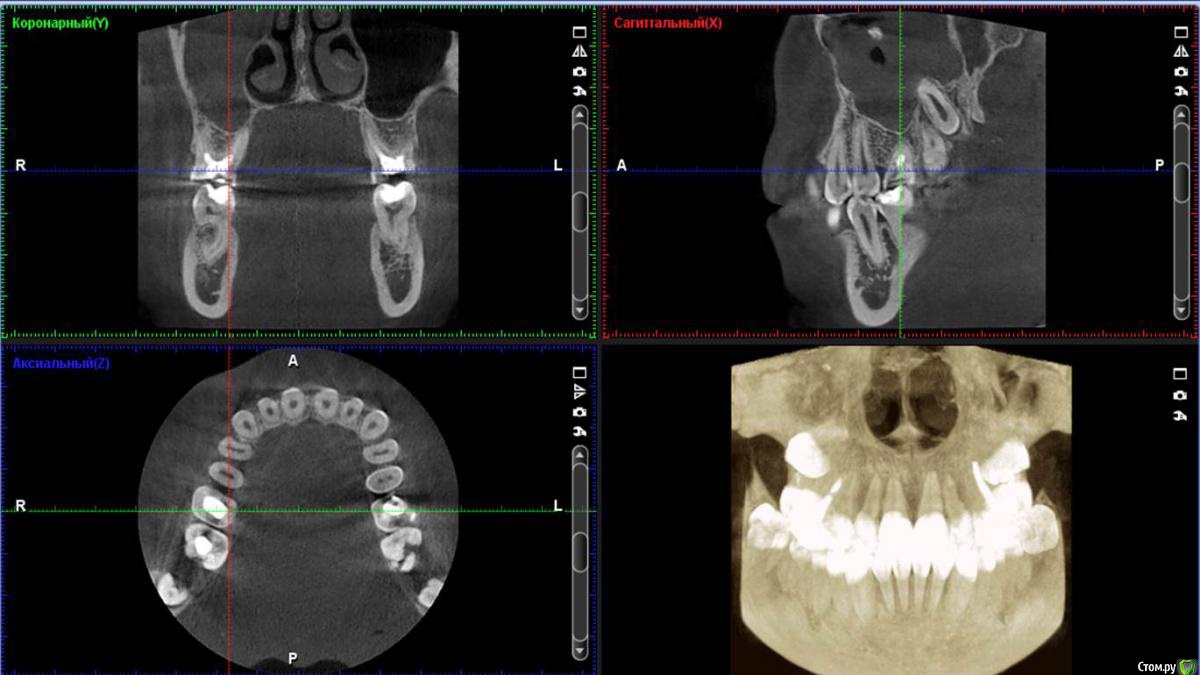

diesel87 Опубликовано 24 ноября, 2015 Поделиться Опубликовано 24 ноября, 2015 Спрошу у терапевтов, сегодня пришла пациентка полечить пульпит в 14, полечили, принесла с собой орто, посмотрел, забавная гранулема в пазухе выросла, причина видимо 16, есть подвижность 1 степени, со стороны неба отмечает периодические выбухания, которые сами проходят. Думаю ей 12 лет, не пациентке. Что скажите господа, эндо имеет смысл? http://fs5.directupload.net/images/151124/2hrfb9kp.jpg http://fs5.directupload.net/images/151124/nf6tk9pj.jpg Ссылка на комментарий

Л Ю С Я Опубликовано 24 ноября, 2015 Поделиться Опубликовано 24 ноября, 2015 Надо кт, может и не связано с зубом Ссылка на комментарий

DmitrySH Опубликовано 24 ноября, 2015 Поделиться Опубликовано 24 ноября, 2015 КТ надо бы, делать эндо, но в голове держать план возможной хирургической реабилитации.14, тоже гранулема. 1 Ссылка на комментарий

Л Ю С Я Опубликовано 26 ноября, 2015 Поделиться Опубликовано 26 ноября, 2015 Так что думаете коллеги, эндо или сначала к ЛОРикам?Сначала кт Ссылка на комментарий